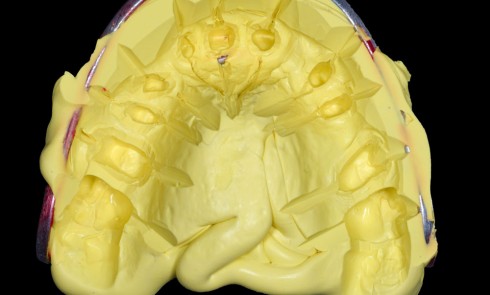

La conduite du traitement endodontique est un domaine où cette analyse en 3D prend toute son importance. Selon Karabucak et al. (2016) [4], le risque de persistance de pathologie péri-apicale est multiplié par quatre lorsqu’un canal a été oublié. Des radiographies excentrées augmentent les chances de découvrir un canal supplémentaire, et ces chances sont…